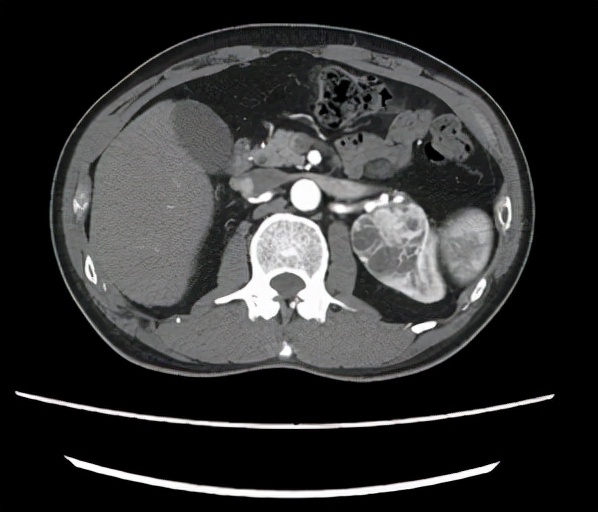

(胡先生的左腎腫瘤)

浙大二院泌尿外科的裘益青主任醫師接診了胡先生。面對胡先生的情況,裘醫生仔細閱片,告訴胡先生他的年齡不大,腎功能尚可,左腎腫瘤形態和密度考慮惡性腫瘤,而且體積較大,位置較深,位於腎門,需行保腎的腫物切除手術,手術難度較大,建議使用達芬奇機器人輔助手術。